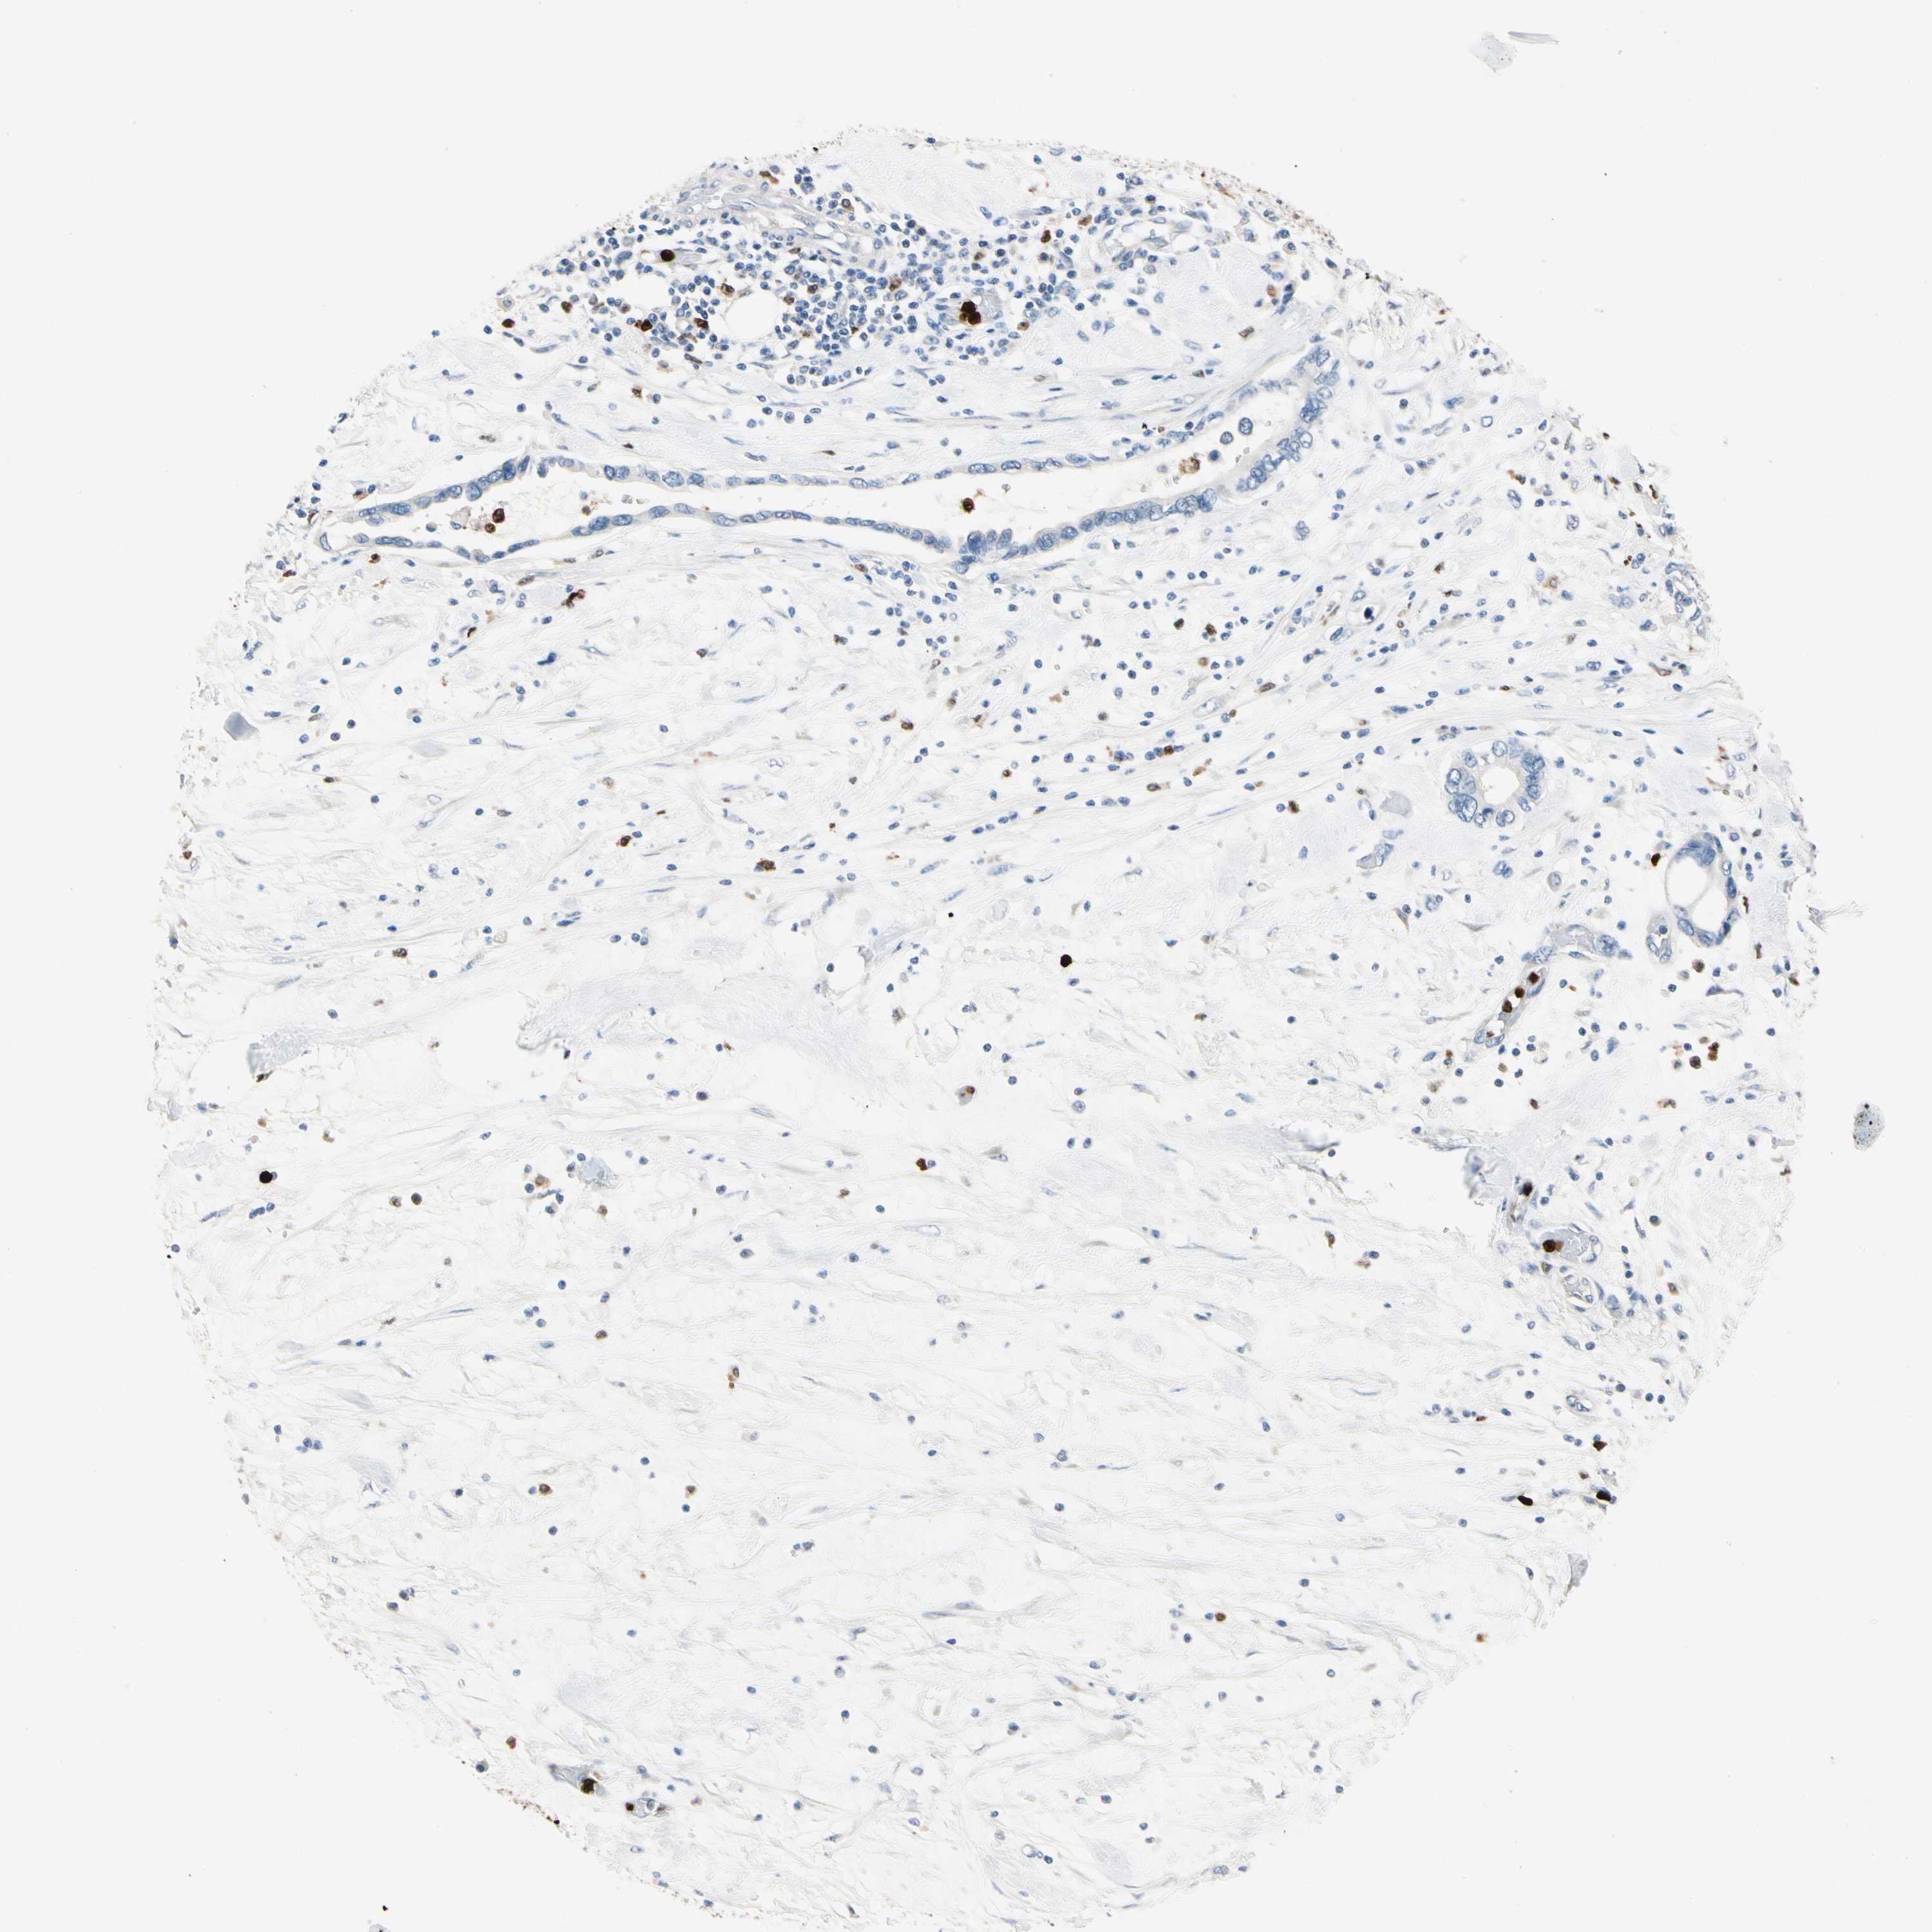

PANCREATIC CANCER - Protein expressioni

A mouse-over function shows sample information and annotation data. Click on an image to view it in a full screen mode. Samples can be filtered based on level of antibody staining by selecting one or several of the following categories: high, medium, low and not detected. The assay and annotation is described here.

Note that samples used for immunohistochemistry by the Human Protein Atlas do not correspond to samples in the TCGA dataset.

Antibody stainingi

Antibody staining in the annotated cell types in the current human tissue is reported as not detected, low, medium, or high, based on conventional immunohistochemistry profiling in selected tissues. This score is based on the combination of the staining intensity and fraction of stained cells.

Each image is clickable and will lead to virtual microscopy that enables deeper exploration of all samples and also displays staining intensity scores, fraction scores and subcellular localization as well as patient and tissue information for each sample.

Antibody HPA008052

Antibody CAB010277

Staining

High

Medium

Low

Not detected

Intensity

Strong

Moderate

Weak

Negative

Quantity

>75%

75%-25%

<25%

None

Location

Nuclear

Cytoplasmic/membranous

Cytoplasmic/membranous,nuclear

Adenocarcinoma, NOS

Adenocarcinoma, metastatic, NOS